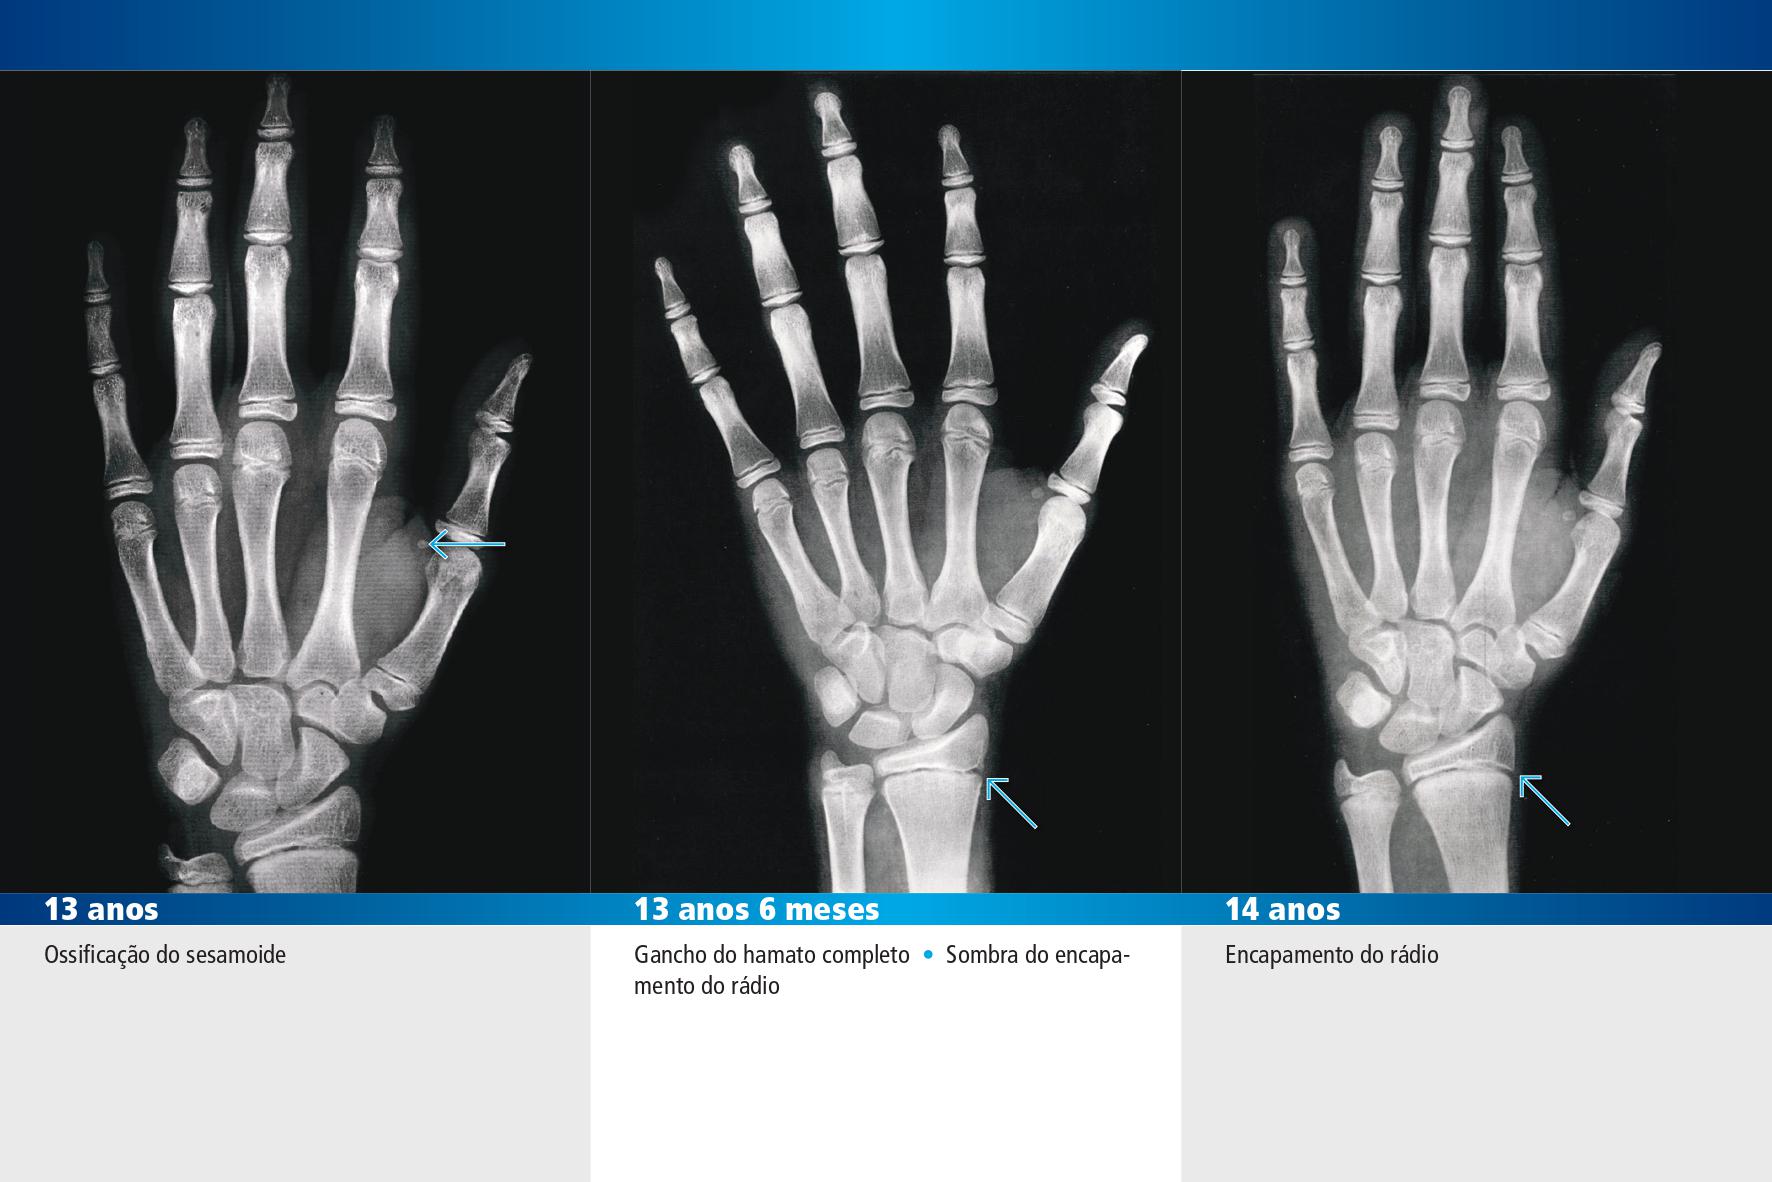

Masculino - 13 anos, 13 anos e 6 meses, 14 anos

Feminino - 12 anos, 13 anos, 13 anos e 6 meses